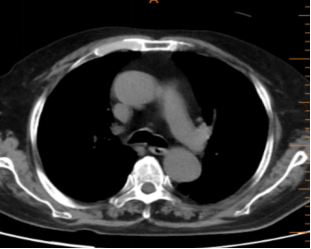

随访11-17胸部CT:

随访12-16胸部CT: